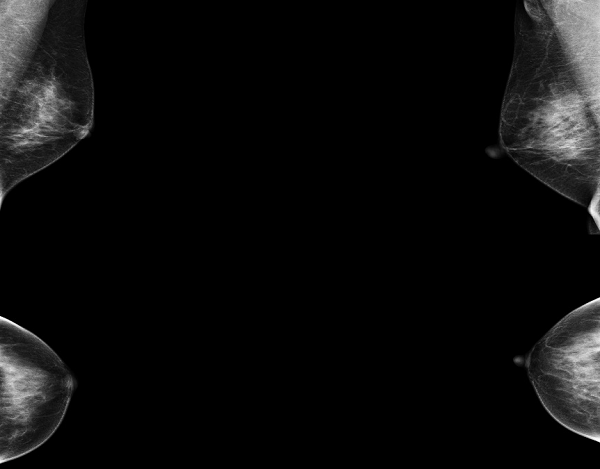

患者A钼靶显示“正常”,但超声发现囊肿和实性结节(如图1、2);

图1 患者A的钼靶图像,报告显示为正常乳腺